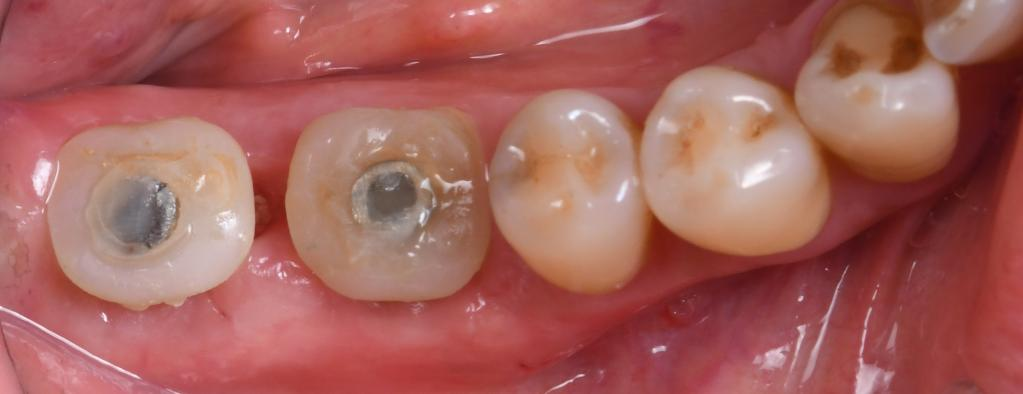

●46、47牙见大面积银汞填充物,边缘密合度差,无松动,叩痛(—),牙髓温度测试无反应

●局麻下,快机磨平牙冠

●种植导板就位贴合

●在种植导板引导下逐级钻孔,植入植体,佩戴个性化愈合基台体